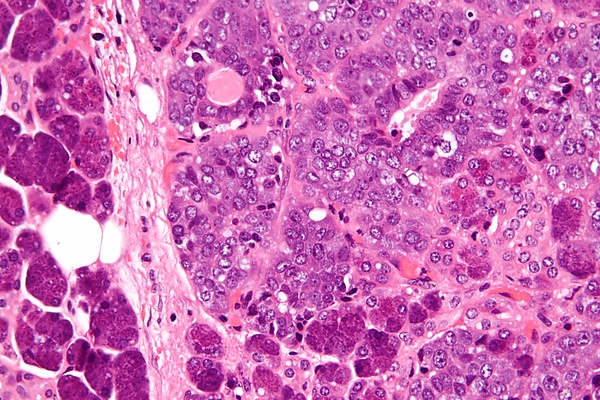

Одной из ключевых особенностей эпителиально-миоэпителиальной карциномы является её «двухфазное» расположение, то есть она имеет два разных типа клеток, расположенных слоями. Внутренний слой, называемый люминальными клетками, представляет собой протоковые клетки с розоватой (эозинофильной) окраской, в то время как внешний слой, известный как миоэпителиальные клетки, часто выглядит прозрачным. Эта слоистая структура может различаться по толщине, от одного слоя до нескольких слоев, и может даже выглядеть сплошной в некоторых областях. Опухоль может иметь различные узоры, такие как крибриформ (с небольшими, ситовидными пространствами), базалоидные (маленькие, плотно упакованные клетки) и двойные прозрачные клеточные слои. В некоторых случаях клетки могут также выглядеть как сальные (вырабатывающие масло) или плоские (плоские) клетки. Клетки показывают только легкие или умеренные отклонения в своих ядра (центральная часть клетки). Это сочетание паттернов и типов клеток помогает патологам идентифицировать эпителиально-миоэпителиальную карциному и отличать её от других опухолей слюнных желез[2].

Клетки опухоли, демонстрирующие трансформацию высокой степени, можно охарактеризовать как нетипичные или плеоморфные. Кроме того, опухоли с высокой степенью трансформации часто имеют более митотические фигуры (опухолевые клетки делятся для создания новых опухолевых клеток) и тип гибели клеток, называемый некроз тоже можно увидеть. Трансформация высокой степени важна, потому что эти опухоли с большей вероятностью метастазировать на лимфатический узел и легкие.